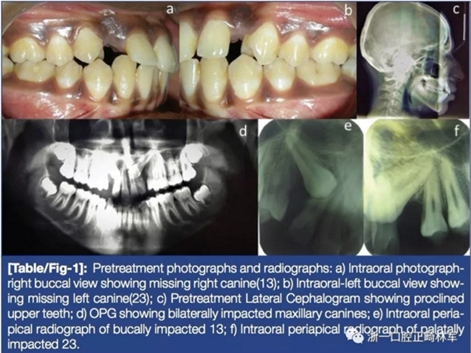

17歲男性患者:骨性安氏I類,安氏I類錯(cuò)合畸形,上下前牙前傾,雙側(cè)上頜尖牙埋伏阻生(右側(cè)頰向阻生、左側(cè)腭向阻生)(圖1)。

治療開始時(shí),患者使用0.022MBT托槽系統(tǒng)及0.016-in 鎳鈦絲。2月后,翻瓣暴露埋伏尖牙,粘結(jié)托槽后縫合全厚瓣并暴露托槽區(qū)域,換用0.016×0.022-in 鎳鈦絲,將頰側(cè)和腭側(cè)尖牙處托槽綁入主絲,用不銹鋼結(jié)扎絲與16托槽鉤相連(圖2)。